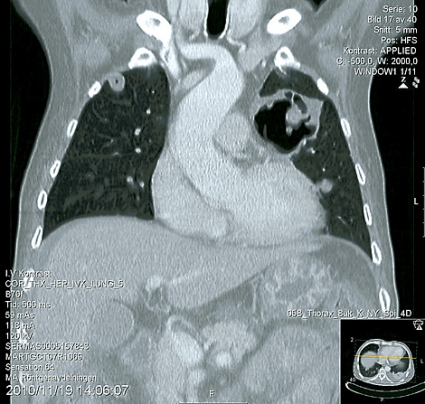

Patienten lades in på infektionskliniken, där han screenades och isolerades avseende multiresistenta bakterier. På misstanke om oral svampinfektion sattes nystatin in. Då patienten hade diarré togs fecesodling och prov för Clostridium difficile. Patienten fick syrgas på grimma. Lungröntgen visade bilaterala avrundade parenkymförändringar av oklar natur (Figur 1). Fynden ingav misstanke om malignitet alternativt tbc, varför man gick vidare med datortomografi av torax, buk och hjärna. DT-hjärna var utan anmärkning, men DT-torax visade en stor kavern i vänster ovanlob och bilateralt flera kaviterande förändringar med vätskenivåer samt en mindre mängd pleuravätska (Figur 2). På DT-buk sågs en ödematös kolonvägg. Clostridium difficile-toxin i feces var positivt, och behandling med metronidazol påbörjades. Svar på sedvanlig fecesodling var negativ. Den neurolog som konsulterades bedömde att patienten hade nedsatt kraft i benen men att han inte var totalt paraplegisk. MR-rygg beställdes.